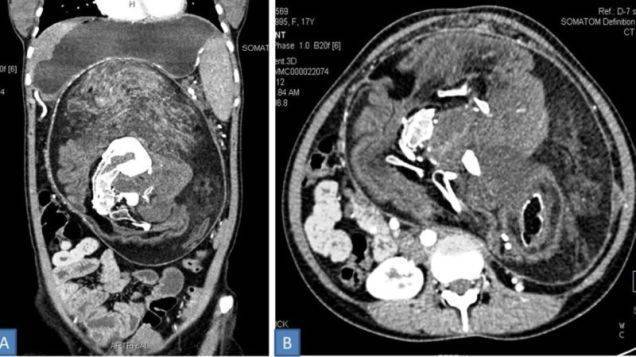

Un fatto incredibile avvenuto ad una ragazza di 17 anni che ha vissuto finora con un fratello gemello nel suo corpo. Un fenomeno molto raro, come hanno rivelato gli specialisti, che si è verificato finora meno di 200 volte. Secondo la pubblicazione del Bmj Case Reports i dottori hanno così tolto dall’addome il gemello che portava dentro di sé da sempre. Il fenomeno, chiamato feuts in fetu, avviene a causa di una ‘rara anomalia dello sviluppo dei feti, e quello malformato si sviluppa all’interno del corpo dell’altro gemello’. La ragazza affermava di sentirsi sazia anche dopo aver mangiato poco soffrendo sempre di dolore all’addome. Così dopo una Tac con contrasto si è notata “una massa ben definita” all’interno del corpo della ragazza.

Un TAC del feto encontrado en el abdomen de la mujerImagen: Kumar, et al (BMJ Case Reports)

Subito dopo gli esami i medici hanno deciso di asportare il corpo del gemello attraverso un intervento chirurgico: l’operazione è stata eseguita alla grande con la rimozione della massa dalle dimensioni di 30x16x10 cm. Il fenomeno è considerato rarissimo e viene riscontrato soprattutto nei bambini: è stata la prima volta in un corpo di una persona quasi adulta. Altri sette casi sono stati osservati negli esseri umani di età superiore ai 15 anni.